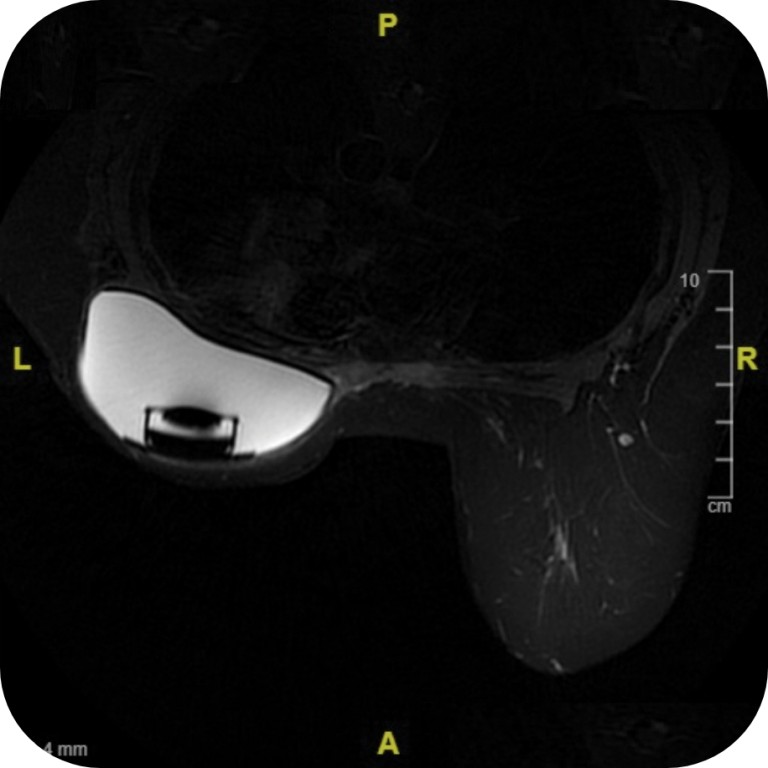

Demonstrated MR Conditional Use

Clinical studies have shown that the Motiva Flora® SmoothSilk® Tissue Expander has no known hazards in specific MR environments with conditions of use (1.5, and 3 Tesla MR systems).2,3

The Motiva Flora® SmoothSilk® Tissue Expander images at high field (3T).

Under the specific MR conditions per labeling, the Motiva Flora® SmoothSilk® Tissue Expander demonstrated no MR-related complications such as discomfort related due to expander displacement, overheating reported, or MR damage to the expander port.2,3

MRI with Motiva Flora® SmoothSilk® Tissue Expander with RFID Port

Motiva Flora® SmoothSilk® Tissue Expanders with the RFID port do not generate distortion of T1 (a) or T2 (b) in weighted axial MRI images*.